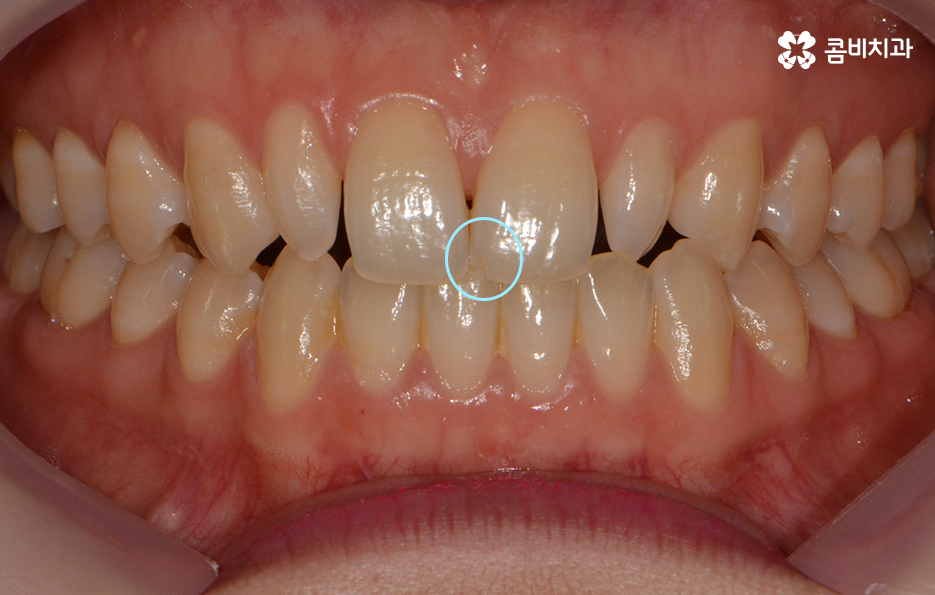

앞니의 깨짐과 왜소치, 전체적인 치열의 개선을 원하셨던 케이스

파란 원 - 치아의 깨짐, 빨간 원 - 왜소치

왜소치란? - 일반적인 치아에 비해 비정상적으로 작은 치아를 의미 합니다. 왜소치가 앞니 부분에 위치한 경우 치아가 벌어져 보이거나 심미적인 부담감을 느끼실 수 있습니다.